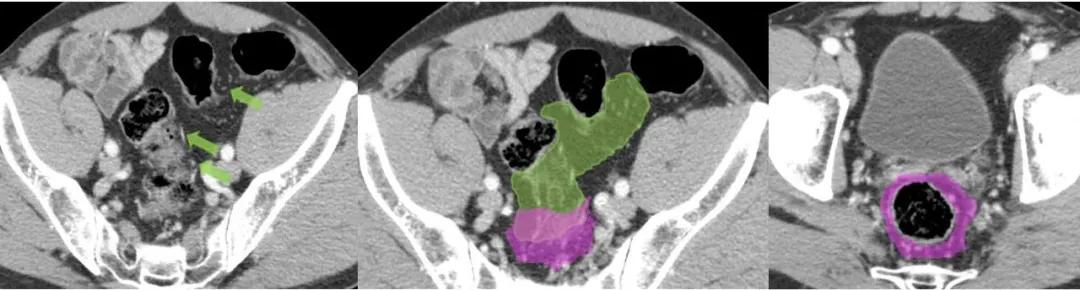

直肠系膜(粉红色)与乙状结肠系膜(绿色)的汇合处。乙状结肠动脉(绿箭头)。